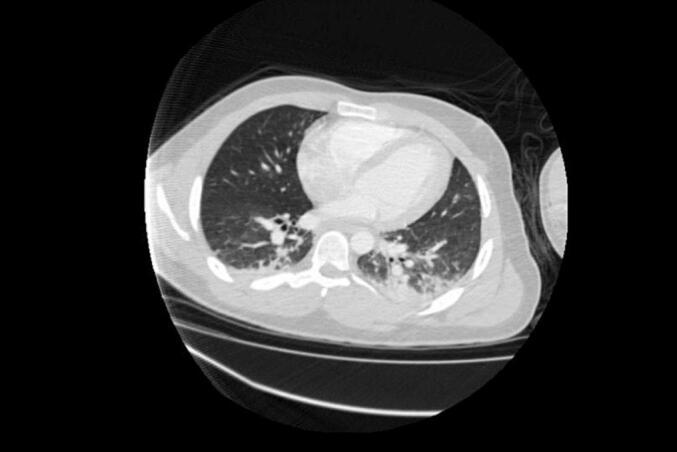

We present a case report of fat embolism syndrome in the Trauma Intensive Care Unit with an atypical presentation. A 21-year-old male patient was admitted with multiple fractures after a motorcycle accident. Shortly after the debridement of the open fracture and external fixation of the bones, the patient presented with hypoxemia, tachypnea, fever, and tachycardia. There were no neurologic abnormalities and no petechial rash. Supportive care, including mechanical ventilation, was required. Initial chest angiotomography did not detect pulmonary thromboembolism. There were discrete bilateral consolidations in the lung bases - no bacterial or viral infection findings, including a negative COVID-19 test. Computed tomography was repeated after 5 days, evidenced by bilateral well-demarcated ground glass opacities. Our case presented an atypical presentation of fat embolism syndrome, without classical signs and symptoms, such as neurologic abnormalities and petechial rash. In this context, other differential diagnoses were considered, since the clinical manifestations of fat embolism are non-specific, and often are seen in other post-traumatic conditions. This case highlights the diagnostic challenges of fat embolism syndrome in the Intensive Care Unit. Atypical presentation must be taken into consideration when treating high-risk patients.

我们报告一例创伤重症监护病房中出现非典型表现的脂肪栓塞综合征病例。一名21岁男性患者在摩托车事故后因多处骨折入院。在对开放性骨折进行清创和骨骼外固定后不久,患者出现低氧血症、呼吸急促、发热和心动过速。未发现神经功能异常,也没有瘀点皮疹。需要进行包括机械通气在内的支持性治疗。最初的胸部血管造影未检测到肺血栓栓塞。肺底部有散在的双侧实变——未发现细菌或病毒感染迹象,包括新冠病毒检测呈阴性。5天后重复进行计算机断层扫描,显示双侧有界限清晰的磨玻璃影。我们的病例呈现出脂肪栓塞综合征的非典型表现,没有神经功能异常和瘀点皮疹等典型症状和体征。在此情况下,由于脂肪栓塞的临床表现不具特异性,且常在其他创伤后情况中出现,因此考虑了其他鉴别诊断。该病例凸显了重症监护病房中脂肪栓塞综合征的诊断挑战。在治疗高危患者时必须考虑非典型表现。